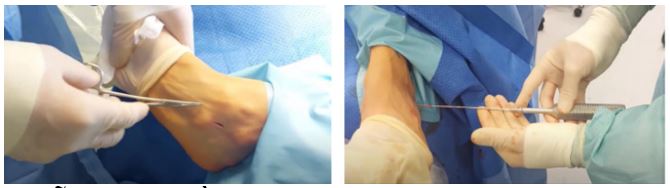

There are various surgical methods available, one of which is the subtalar joint elevation surgery, currently being effectively applied at FV Hospital. This procedure involves inserting a screw into the subtalar joint space to limit excessive rotation of the talus bone on the calcaneus. This is a simple procedure that takes only 5 to 15 minutes and delivers high effectiveness. “FV has performed this surgery on 50 patients with good outcomes, and the patients have been satisfied after treatment.” Dr Khiem shared.

Surgical Treatment for Flat feet at FV Hospital